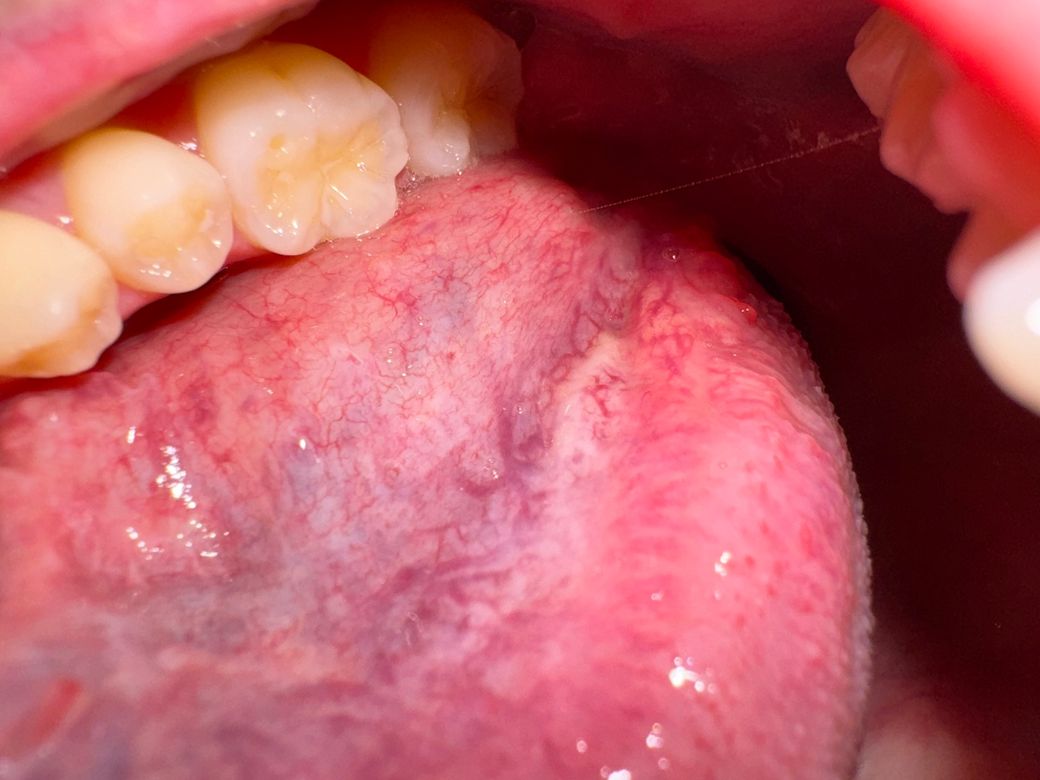

혀 백반증인지...설암 초기증상인지..정상조직인지..

26세 남성입니다ㅠㅠ

아이코스 전자담배를 흡연하고있고

흡연한지는 7년째인데

백반증이나 설암 초기증상인건가요? ㅠㅠ

전혀 아프지도않고 피도안나고 일반 혀 표면처럼 평평합니다 덩어리지지않았어요 염증도 난적없었구요

혀를 세게 이리저리 움직이면 하얘지기도하고 가끔 연해져보이기도하는데 일반적으로 혀를 내밀었을 때 저렇게 하얗게보이고

자꾸 신경쓰여서요ㅠㅠ 혀에 약간 힘을주면 하얀게 더 선명해지는 느낌입니다.